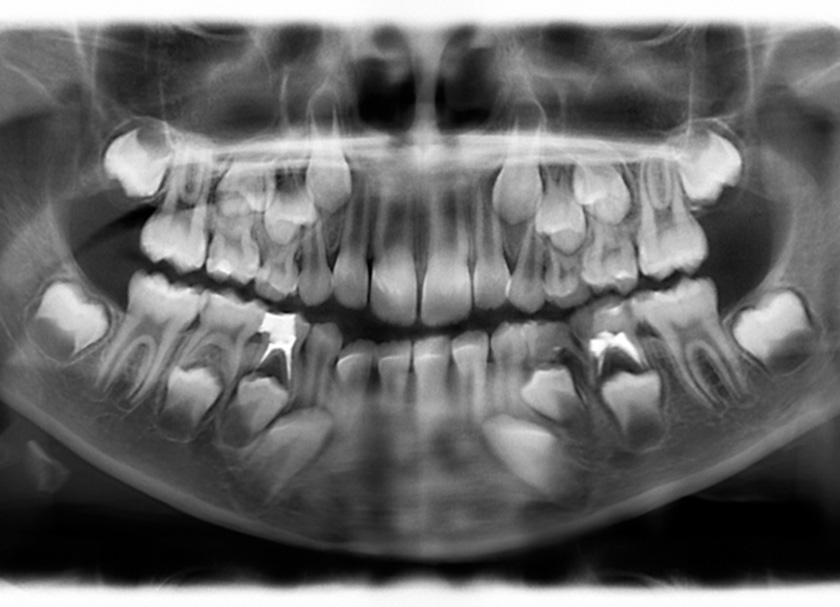

It is essential to take your kids to the pediatric dentist for frequent checks and teach them how to floss and brush their teeth properly. Every visit would involve a complete cleaning, x-rays, and a thorough examination of mouth. Early cavity detection allows your dentist to repair the issue with a less intrusive procedure, like a tooth filling, instead of requiring a full pulpectomy.